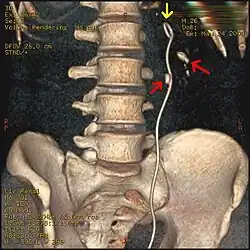

A ureteral stent (pronounced you-REE-ter-ul), or ureteric stent, is a thin tube inserted into the ureter to prevent or treat obstruction of the urine flow from the kidney. The length of the stents used in adult patients varies between 24 and 30 cm. Additionally, stents come in differing diameters or gauges, to fit different size ureters. The stent is usually inserted with the aid of a cystoscope. One or both ends of the stent may be coiled to prevent it from moving out of place; this is called a JJ stent, double J stent or pig-tail stent.